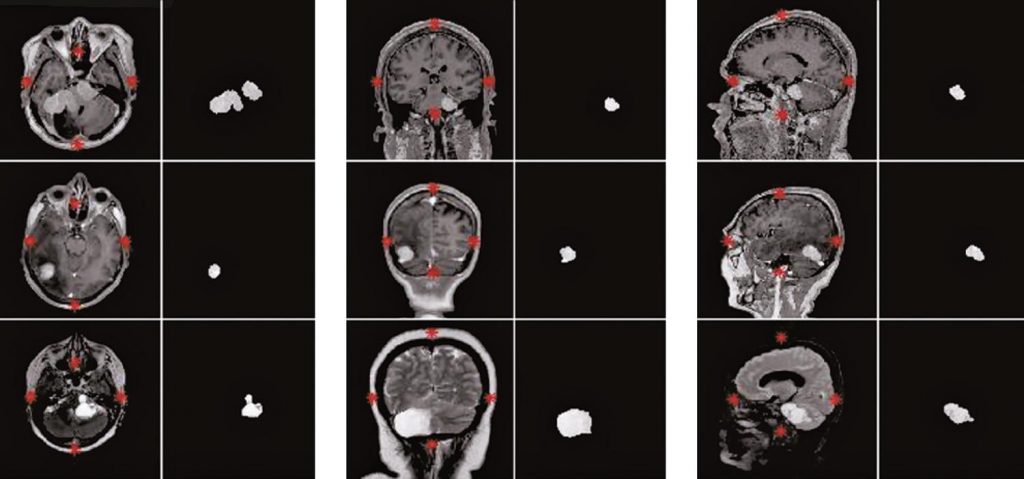

A total of 130 magnetic resonance images were used in the T1c, T2 and FSPRG T1C sequences and in the axial, sagittal and coronal planes of patients with brain cancer. The algorithms employed contrast correction, histogram normalization and binarization techniques to disconnect adjacent structures from the brain and enhance the region of interest. Automatic segmentation was performed through detection by coordinates and arithmetic mean of the area. Morphological operators were used to eliminate undesirable elements and reconstruct the shape and texture of the tumor. The results were compared with manual segmentations by two radiologists to determine the efficacy of the algorithms implemented.

The correlated correspondence between the segmentation obtained and the gold standard was 89.23%.